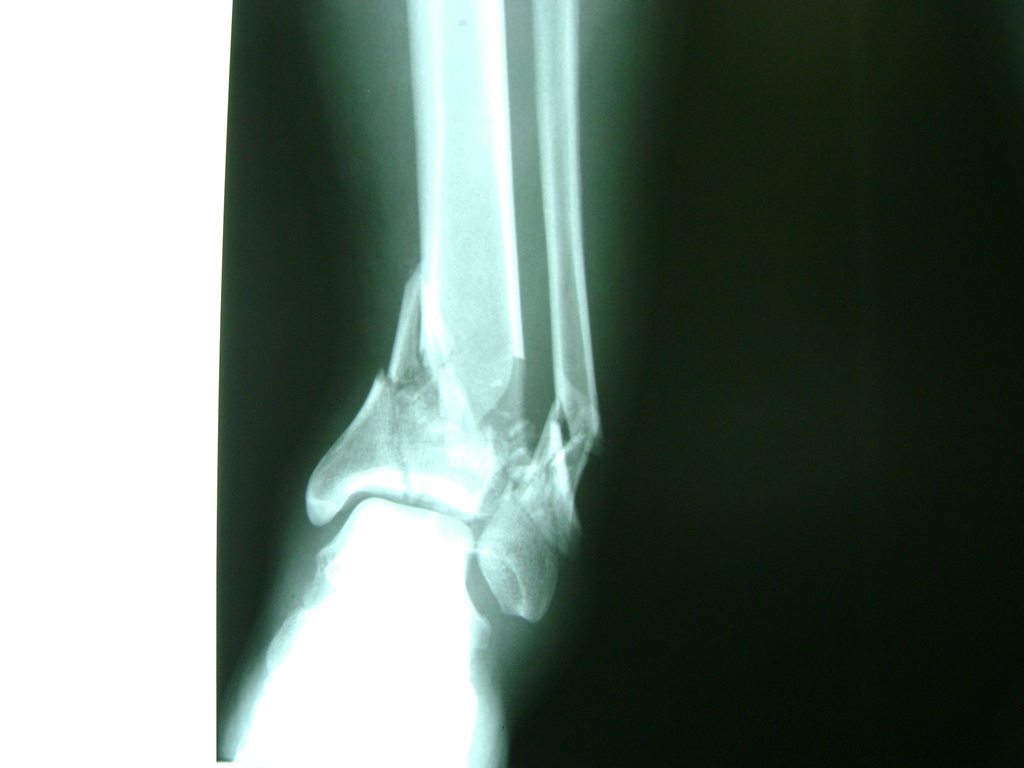

Una fractura de tobillo es la rotura de uno o más de los huesos del tobillo. Estas fracturas pueden ser:

- Parciales (el hueso está sólo parcialmente fisurado, no del todo).

- Completas (el hueso está perforado y está en 2 partes).

- Los extremos de los huesos están desalineados entre sí (desplazados).

- La fractura se extiende hasta la articulación del tobillo (fractura intra-articular).